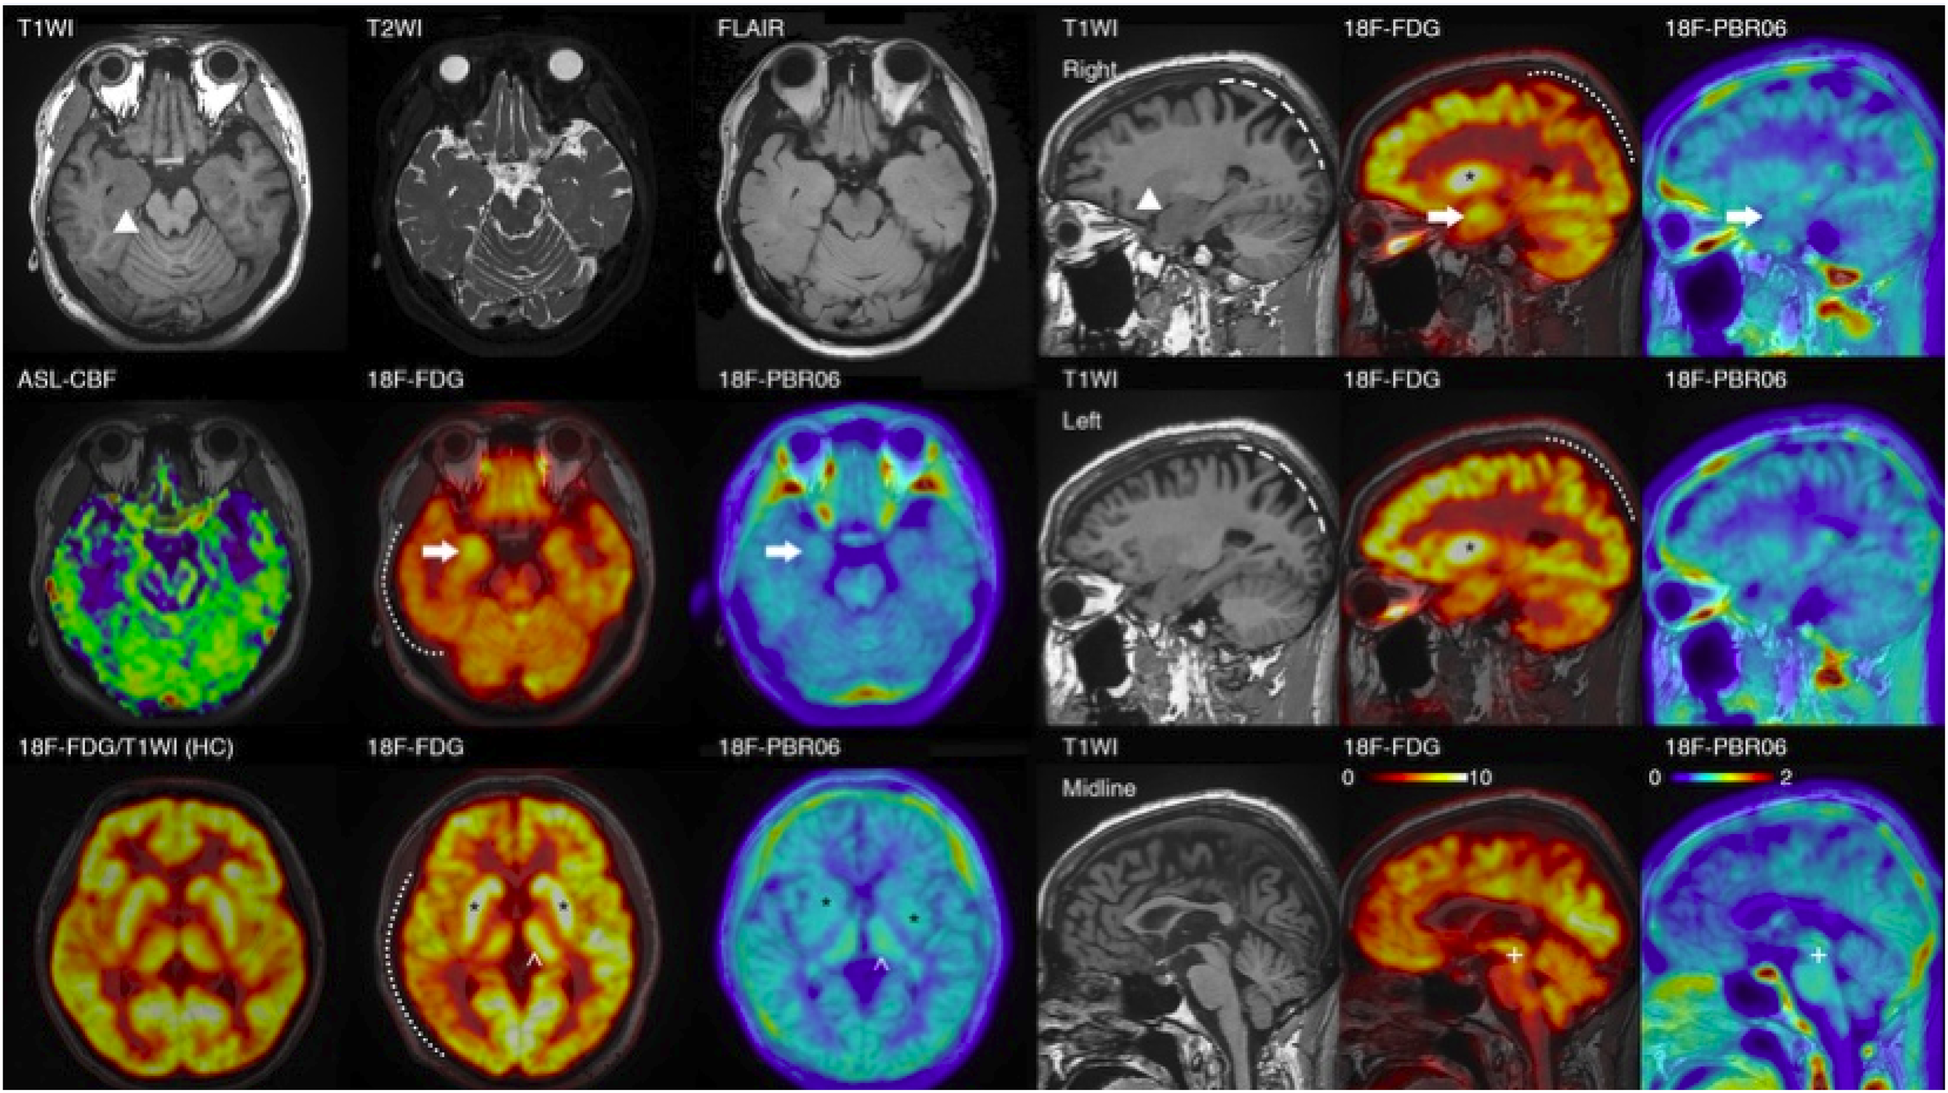

Figure 3

PET/MRI images of the patient. The PET/MRI imaging displays decreased FDG absorption in the cortex of the right hemisphere and the left parietal lobe (indicated by a dotted line). It also shows atrophy in both parietal lobes (marked by a dashed line) in the patient with encephalitis. Regarding focal changes, the volume of the hippocampus on both sides has increased (▴), with heightened FDG and TSPO uptake (→), particularly on the right. However, no noticeable abnormalities were detected in T2\FLAIR\ASL scans. Additionally, there is increased FDG and TSPO uptake in the bilateral basal ganglia (*), and the left thalamus (^). (In comparison with the bottom-left control: the uptake in the cortex and basal ganglia are essentially equivalent, but the patient's basal ganglia-to-cortex ratio is markedly elevated); the FDG\TSPO uptake in the midbrain is also enhanced (+).

Physical examination during his hospitalization revealed no abnormal findings in his cognitive function. CSF tests showed normal cell count, protein, glucose, and chloride levels. Long-term electroencephalogram (EEG) examination revealed epileptiform electrical discharges in the right frontal and anterior temporal areas, and slowing waves in the right frontal and the temporal areas (Figure 1). Magnetic resonance imaging (MRI) of the brain showed enlargement of the right amygdala and hippocampi (Figure 2). To further evaluate changes in the brain, positron emission tomography/magnetic resonance imaging (PET/MRI) scans using 18F-FDG and TSPO were performed. These scans showed increased volume, metabolism, and TSPO uptake in the medial temporal lobes. Increased metabolism was also observed in the basal ganglia, left thalamus, left temporoparietal junction, midbrain, and localized cerebellum on the right. In contrast, decreased metabolism was observed in the right cerebral hemisphere and left parietal lobe. Additionally, increased TSPO uptake was detected in the left localized frontal lobe, bilateral insular lobes, and both medial temporal lobes (Figure 3). The PET/MRI scans did not detect any tumors, and no tumor markers were found in the patient's serum. Anti-GAD65 IgG antibodies were detected in both the serum and CSF, with antibody titers of 1:100 and 1:30, respectively (Figure 4).